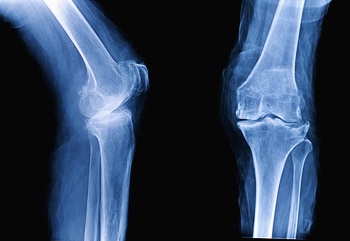

골관절염 정의

골관절염은 퇴행성 관절 질환으로 사용 정도에 따른 점진적인 관절연골의 소실, 또는 변화되는 증상을 동반합니다. 우리 몸의 관절에는 충격을 흡수하는 관절연골이 있는데요. 이러한 연골의 변화로 관절을 구성하는 뼈, 인대, 관절막 등에 2차적인 손상이 생겨 통증이나 기능 장애를 일으킵니다.

골관절염은 특정 관절 부위에 발생하는 일차성 관절염과 외상이나 질병, 기형이 원인이 되는 이차성 관절염으로 나누어지는데요. 발생 빈도는 60세 이상부터 크게 높아집니다. 나이가 많아질수록 발생률이 높으며 남성보다는 여성에게 더 많이 나타납니다.